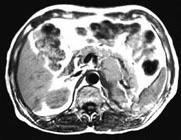

- 多项选择题女,34岁, 无意中发现血压升高4 个月就诊,行CT检查, 如图所示,下列说法正确的是 ( )

A、CT示左侧肾上腺区可见一等密度块影,边界清楚

B、增强扫描,该病灶周边明显强化,中心处强化不明显

C、考虑为左肾上腺腺瘤

D、考虑为左肾上腺嗜铬细胞瘤

E、考虑为左肾上腺转移瘤